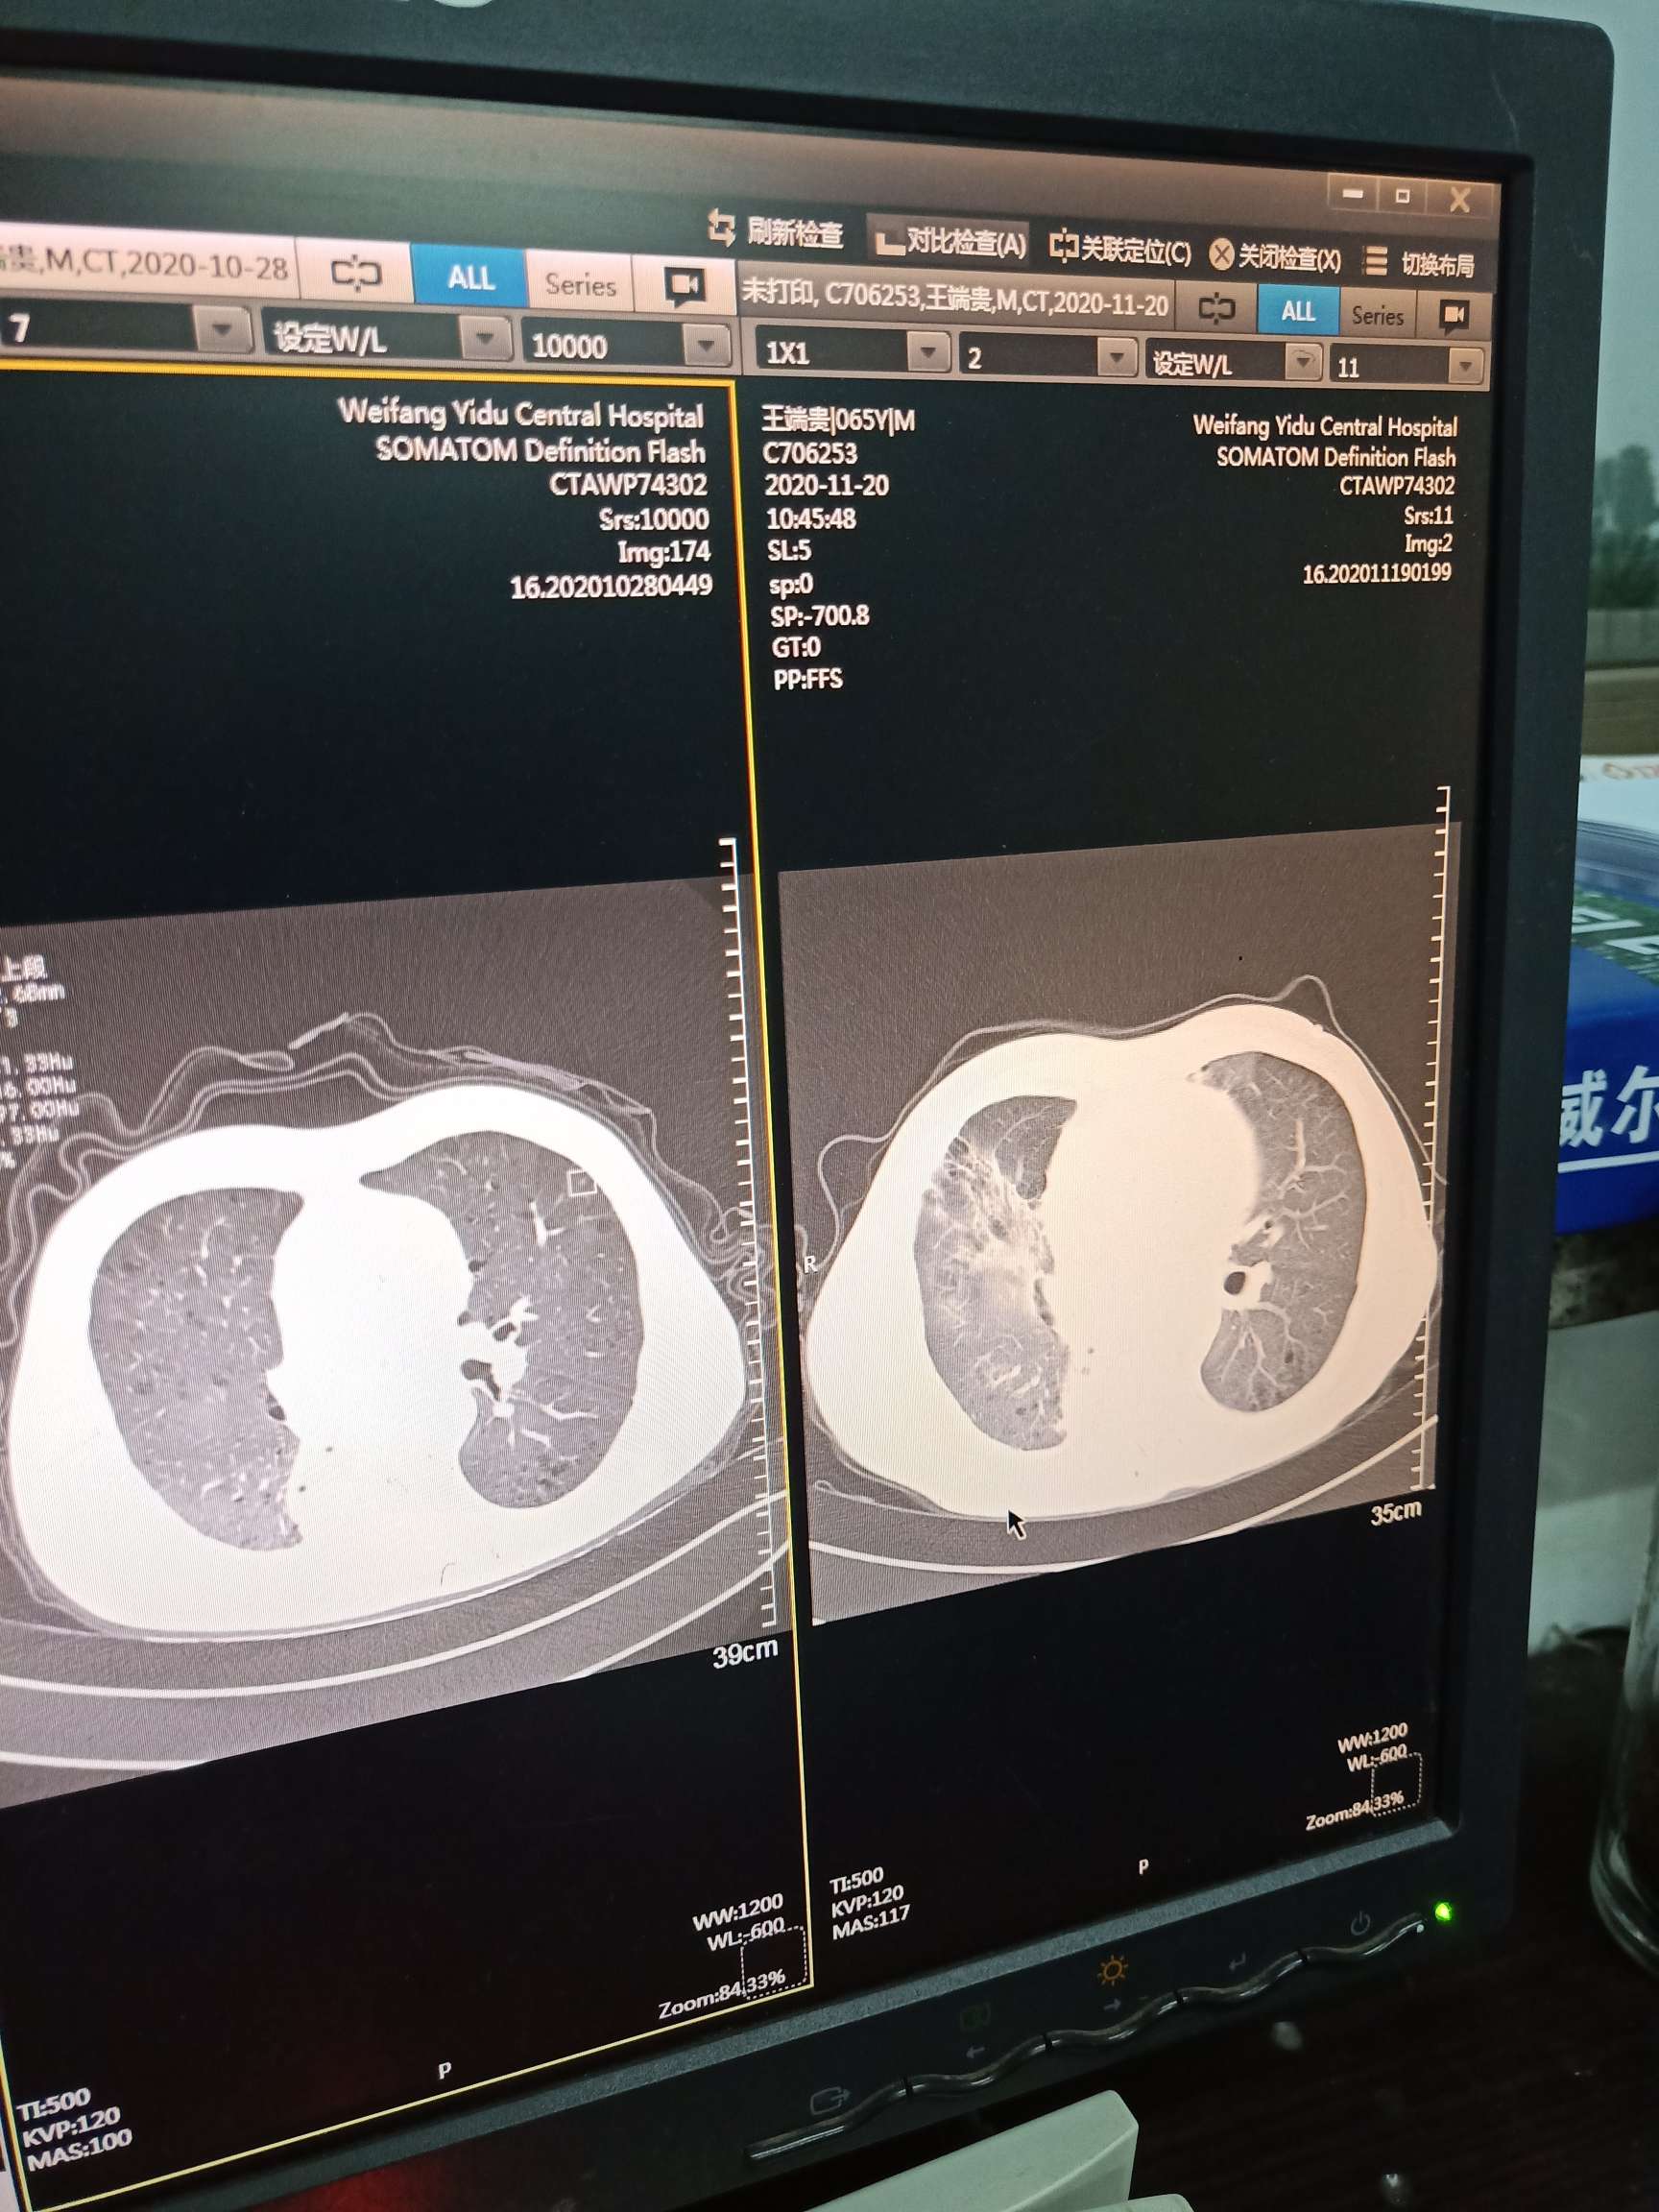

刚才去打印出ct片子加报告单,显示间质性肺炎。二十天前的ct片子显示放射性肺炎明显好转,感觉就快完全好了,一个感冒又两肺爆发肺炎。

这次肿瘤标志物三项超出正常值,因为偶尔会头晕恶心,预约了明天的核磁共振。下图分别是这次的ct报告单,前后两次ct片子对比,这次肿瘤标志物。